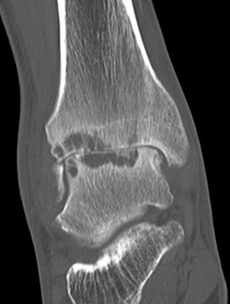

CT

Evaluate bone stock to determine if TAR is appropriate